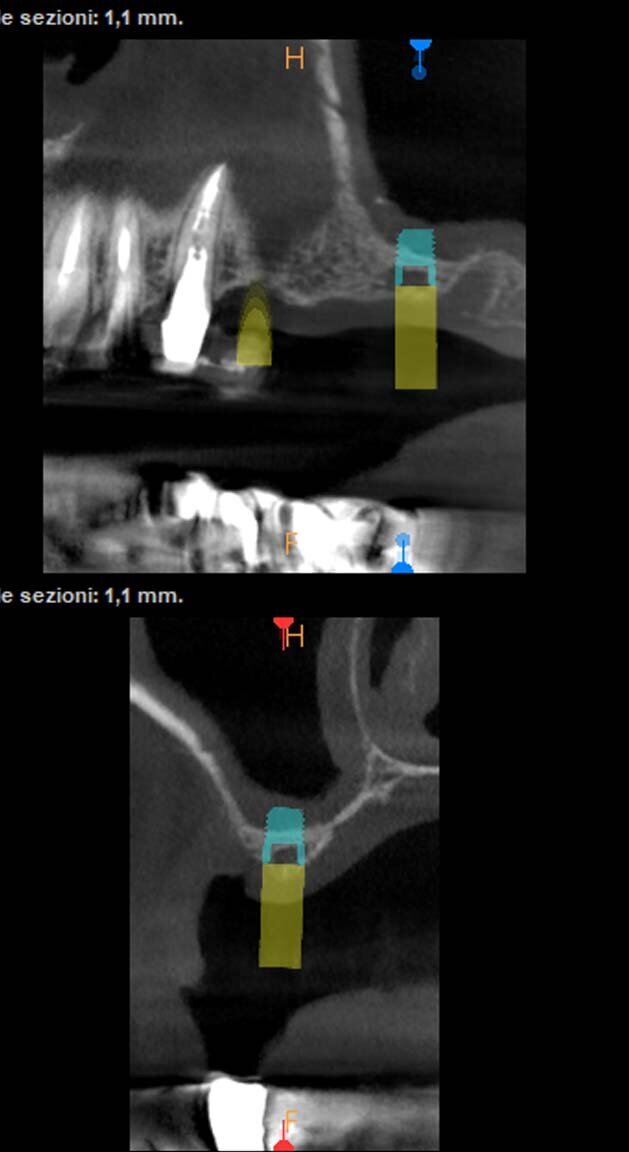

Il paziente di 50 anni in buono stato di salute, necessitava di una riabilitazione di tutta l’arcata superiore sia con impianti nei settori posteriori sia con corone sui denti frontali. Mentre nel sestante superiore destro era presente una quantità d’osso ideale per l’inserimento di impianti di diametro e lunghezza considerati standard, nel sestante sinistro era presente una quantità d’osso insufficiente sia verticalmente che orizzontalmente (Figg. 1-4). A causa dei timori del paziente sono stati esclusi interventi invasivi per incrementare i volumi ossei e si è deciso di inserire in posizione 24 un impianto BTI 3.0 3,3 x 10 mm e in posizione 26 un impianto BTI standard 3,7 x 5,5 mm con un minirialzo contestuale del seno mascellare.

È stato eseguito un lembo a spessore totale senza tagli verticali di rilascio e una regolarizzazione della cresta ossea per mezzo di un raschietto per osso, che ha permesso di ottenere una quantità ulteriore di osso oltre a quello ottenuto per mezzo della fresatura a basso numero di giri secondo la procedura BTI. L’osso ottenuto è stato mischiato con gel piastrinico ottenuto mediante centrifugazione del sangue del paziente secondo la metodica PRGF Endoret ed inserito in parte all’interno dell’osteotomia del dente 26 a protezione della membrana sinusale e in parte protezione della parete ossea vestibolare del dente 24 che era particolarmente sottile. Dopo aver applicato i tappi di guarigione i lembi sono stati suturati per ottenere una guarigione sommersa (Figg. 5-7). Dopo quattro mesi di guarigione gli impianti furono scoperti e due pilastri Multi-im sono stati avvitati con i relativi tappi di guarigione.